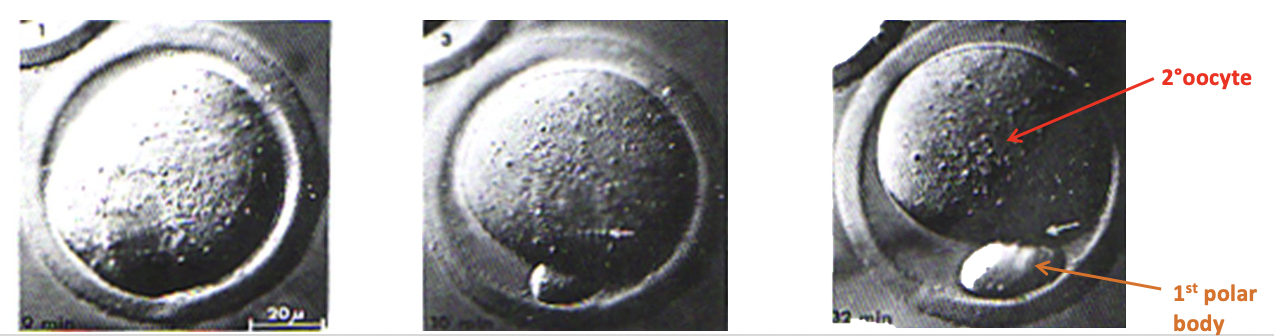

What happens to the nucleus of the oocyte in response to the LH surge?

In response to LH surge, the oocyte nucleus in the DF completes the 1st meiotic division

This division is uneven; ½ chromosomes end up in the oocyte (big cytoplasm), and ½ end up in a small package called the 1st polar body.

Oocyte is now a secondary oocyte

The 1st polar body= now irrelevant + will not divide again, whilst the secondary oocyte starts 2nd meiotic division before arresting (meiosis 2 only occurs in fertilisation)

The 1st division is unequal bc the oocyte needs all the organelles, esp mitochondria for energy!